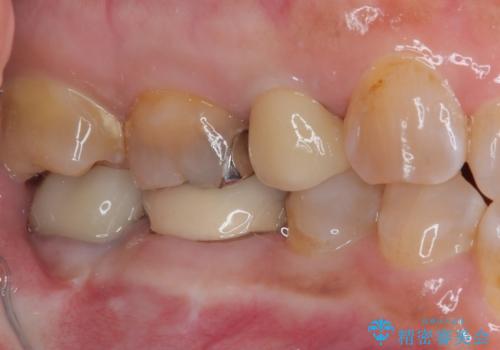

目立つ銀歯をセラミッククラウンに

銀歯を外したところ、土台にほとんどむし歯はなかったため、土台のやり替えを行うことなく、セラミッククラウンを装着しました。